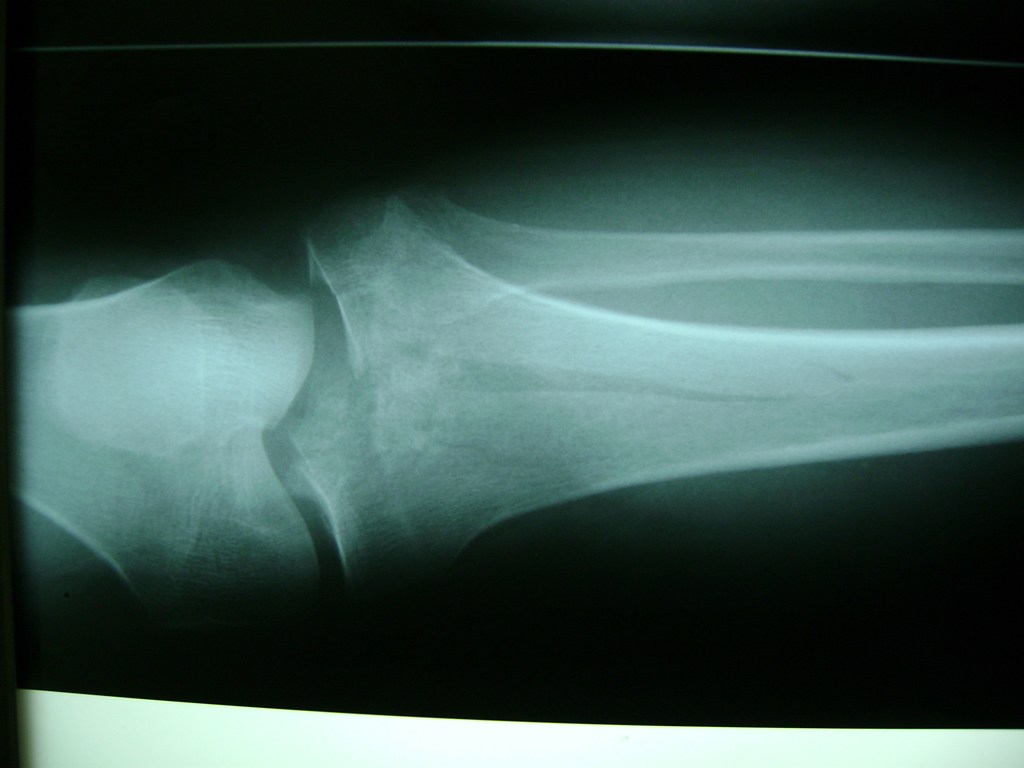

Cirugía de Tibia y Peroné

La artroscopia de rodilla es un cirugía en el cual la estructura interna de la articulación es examinada ya sea para realizar un diagnostico o para realizar un tratamiento, este procedimiento se realiza utilizando un instrumento parecido a un pequeño tubo llamado artroscopio.